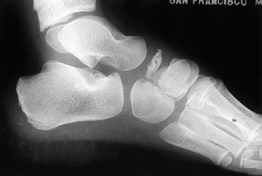

Smillie’s classification is based on the anteroposterior and oblique

radiographs (20,21).

In stage I, there is a fissure fracture of the ischemic epiphysis; in

stage II, there is central depression of the head from bone resorption;

in stage III, there is further collapse of the head with residual

projections of the sides, and the plantar cartilage remains intact; in

stage IV, the plantar portion of articular cartilage separates into a

loose body; and stage V is the final stage, with arthritis, deformity,

and flattening of the metatarsal head (Fig. 119.1).

Figure 119.1. Radiograph showing the typical appearance of Freiberg’s infraction, with a large metatarsal head, flattening, and osteophytes.